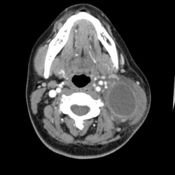

Surgery is considered a great and effective treatment method of lingual tonsil cancer. It is a medical process that basically removes harmful tumor from the oropharynx or tonsil. Many doctors perform tonsil surgery if there is a presence of tumor. Removing the tumor is the way to treat tonsil cancer.